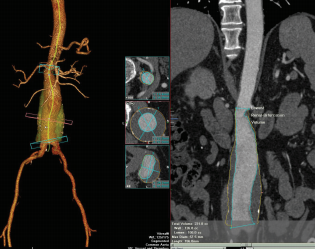

March 6, 2014 — Vital Images Inc., a Toshiba Medical Systems Group Company, is expanding in the EMEA market with an increasing number of organizations migrating to Vital's VitreaAdvanced solution to help improve efficiency, communication and patient care. The VitreaAdvanced advanced visualization solution provides 2-D, 3-D and 4-D images for applications addressing cardiovascular, neurovascular and oncology disease states. Fueled by intelligent automation, it utilizes a clinical workflow to improve speed and simplicity of use.